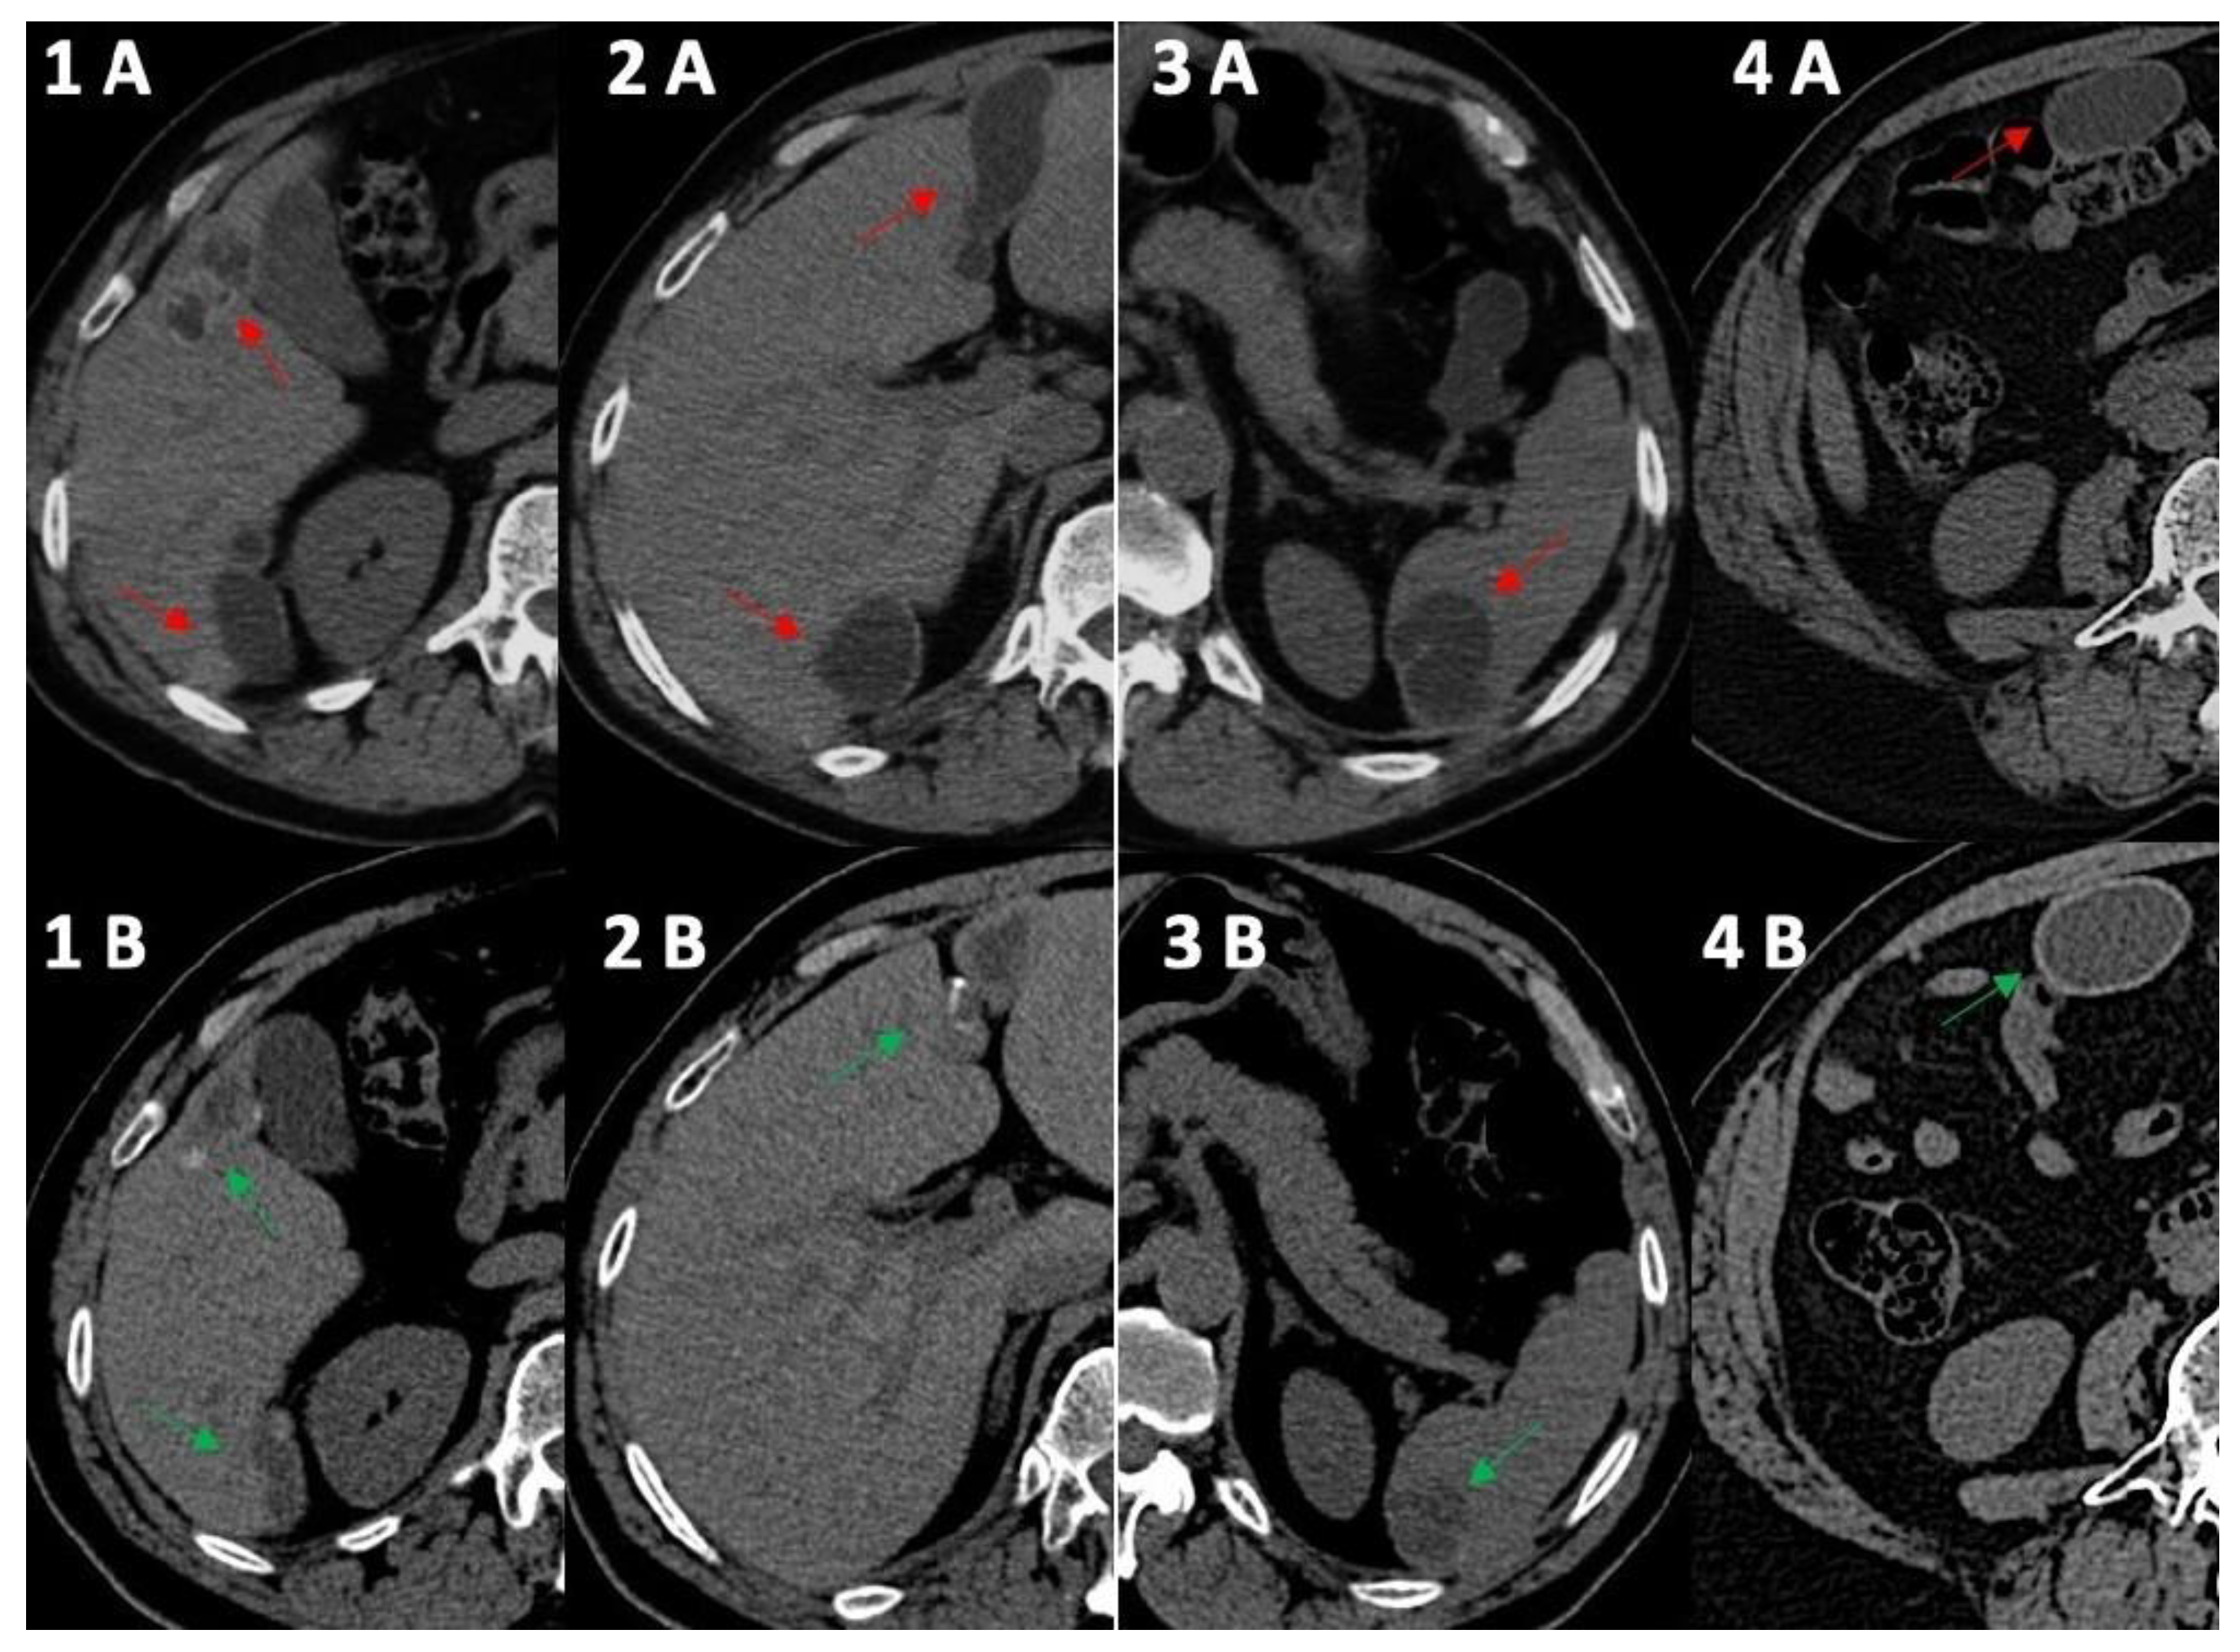

Figure 1.

Computed tomography comparative imaging of some Echinococcus cysts in 2011 (A, red arrow) and in 2021 (B, green arrow). The cysts are located in liver segments 5 ((1A) 15 × 35 mm vs. (1B) 15 × 20 mm) and 6 (1–(2A) 41 × 45 mm vs. (1B) 10 × 36 mm), in segments 3–4 ((2A) 20 × 68 mm vs. 2B 19 × 45 mm), in the upper pole of the spleen ((3A) 30 × 40 mm vs. (3B) 30 × 30 mm), and in the right inframesocolic space ((4A) 41 × 22 mm vs. 4B 40 × 26 mm). In 2021, CT scans (1B,2B,3B) showed some initial signs of cystic wall calcifications that were not present in 2011 (1A, 2A, 3A). Uncertainty persisted for the right inframesocolic cyst (4B), but in 2023 (Figure 2, #3), US demonstrated signs of intracystic degenerative content (Figure 2—n3).

In 2014, the anti-Echinococcus titers were still elevated, serum AST, ALT and GGT were normalized and imaging of the cysts suggested possible activity especially for the peritoneal localizations; therefore, treatment with ABZ was re-started and continued until 2021. Normal hepatic blood test results were observed until the end of treatment with ABZ in 2021 (Table 1) and a final (2021) hepatic FibroScan demonstrated normal stiffness values (May 2021, 2.8 kPa). We observed no significant change in the eosinophil count for the whole duration of the follow-up (Table 1), thus excluding a significant relationship between eosinophilia in this case of cystic echinococcosis [10]. Finally, at the end of 2021, the patient had received a total of 15 complete cycles with ABZ that equaled 1260 days of treatment. All cystic lesions progressively showed US [11] and CT signs of regression (Figure 1 and Figure 2) with some uncertainty for peritoneal lesions, which are still in follow-up in 2023. In particular, based on WHO-IWGE US classification [11], in 2023, all cysts were defined as inactive (CE4–5; Figure 2, frame 1, 2, 4, 5) with the exception of the peritoneal lesion that was considered transitional (CE3; Figure 2, frame 3).